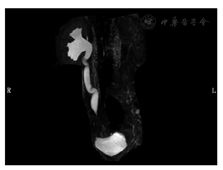

入院后查体:体温39 ℃,消瘦(体重指数16.65 kg/m2),中下腹轻压痛,腰骶部可见3处皮肤瘘口伴脓性分泌物。血白细胞计数8.51×109/L,中性粒细胞比例84.2%,血红蛋白69 g/L,血小板计数335×109/L。白蛋白24 g/L,红细胞沉降率87 mm/h,C反应蛋白120 mg/dl。腰骶部脓性分泌物培养结果示肺炎克雷伯菌、光滑假丝酵母菌阳性。结肠镜进镜至距肛缘约60 cm见结肠内瘘口,局部肉芽组织增生,降结肠及脾曲见另两处瘘口形成(图1)。窦道造影可见水溶性造影剂经皮进入窦道,中下腹部多发窦道显影,与小肠、横结肠相通(图2)。小肠CT示克罗恩病术后改变,空肠、盆组回肠克罗恩病活动期改变伴小肠-结肠管内瘘形成,病变肠管与双侧髂肌、右侧闭孔内肌、骶前区多发瘘管形成;骶骨周围、左侧坐骨直肠窝蜂窝织炎及脓肿;双侧臀大肌多发脓肿;右侧输尿管下段与病变肠管粘连,右侧输尿管积水(图3)。磁共振尿路造影示右侧输尿管下段狭窄伴右肾及输尿管中上段扩张积水(图4)。